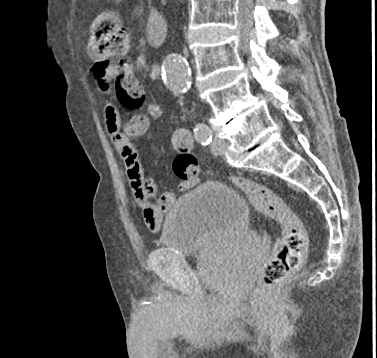

刘春晓教授接诊后,为陈大爷完善盆腔CT血管造影检查,发现他的前列腺体积已达到67×55×58毫米。据了解,正常年轻男性的前列腺大概就板栗大小,从40岁以后前列腺会逐渐增大。由于陈大爷已过百岁,他的前列腺也增大明显,已经达到了鹅蛋的大小,增生的前列腺挤压尿道,导致陈大爷排尿困难,膀胱内残余尿量增多,还有双肾积水等问题,需要尽快进行手术治疗。